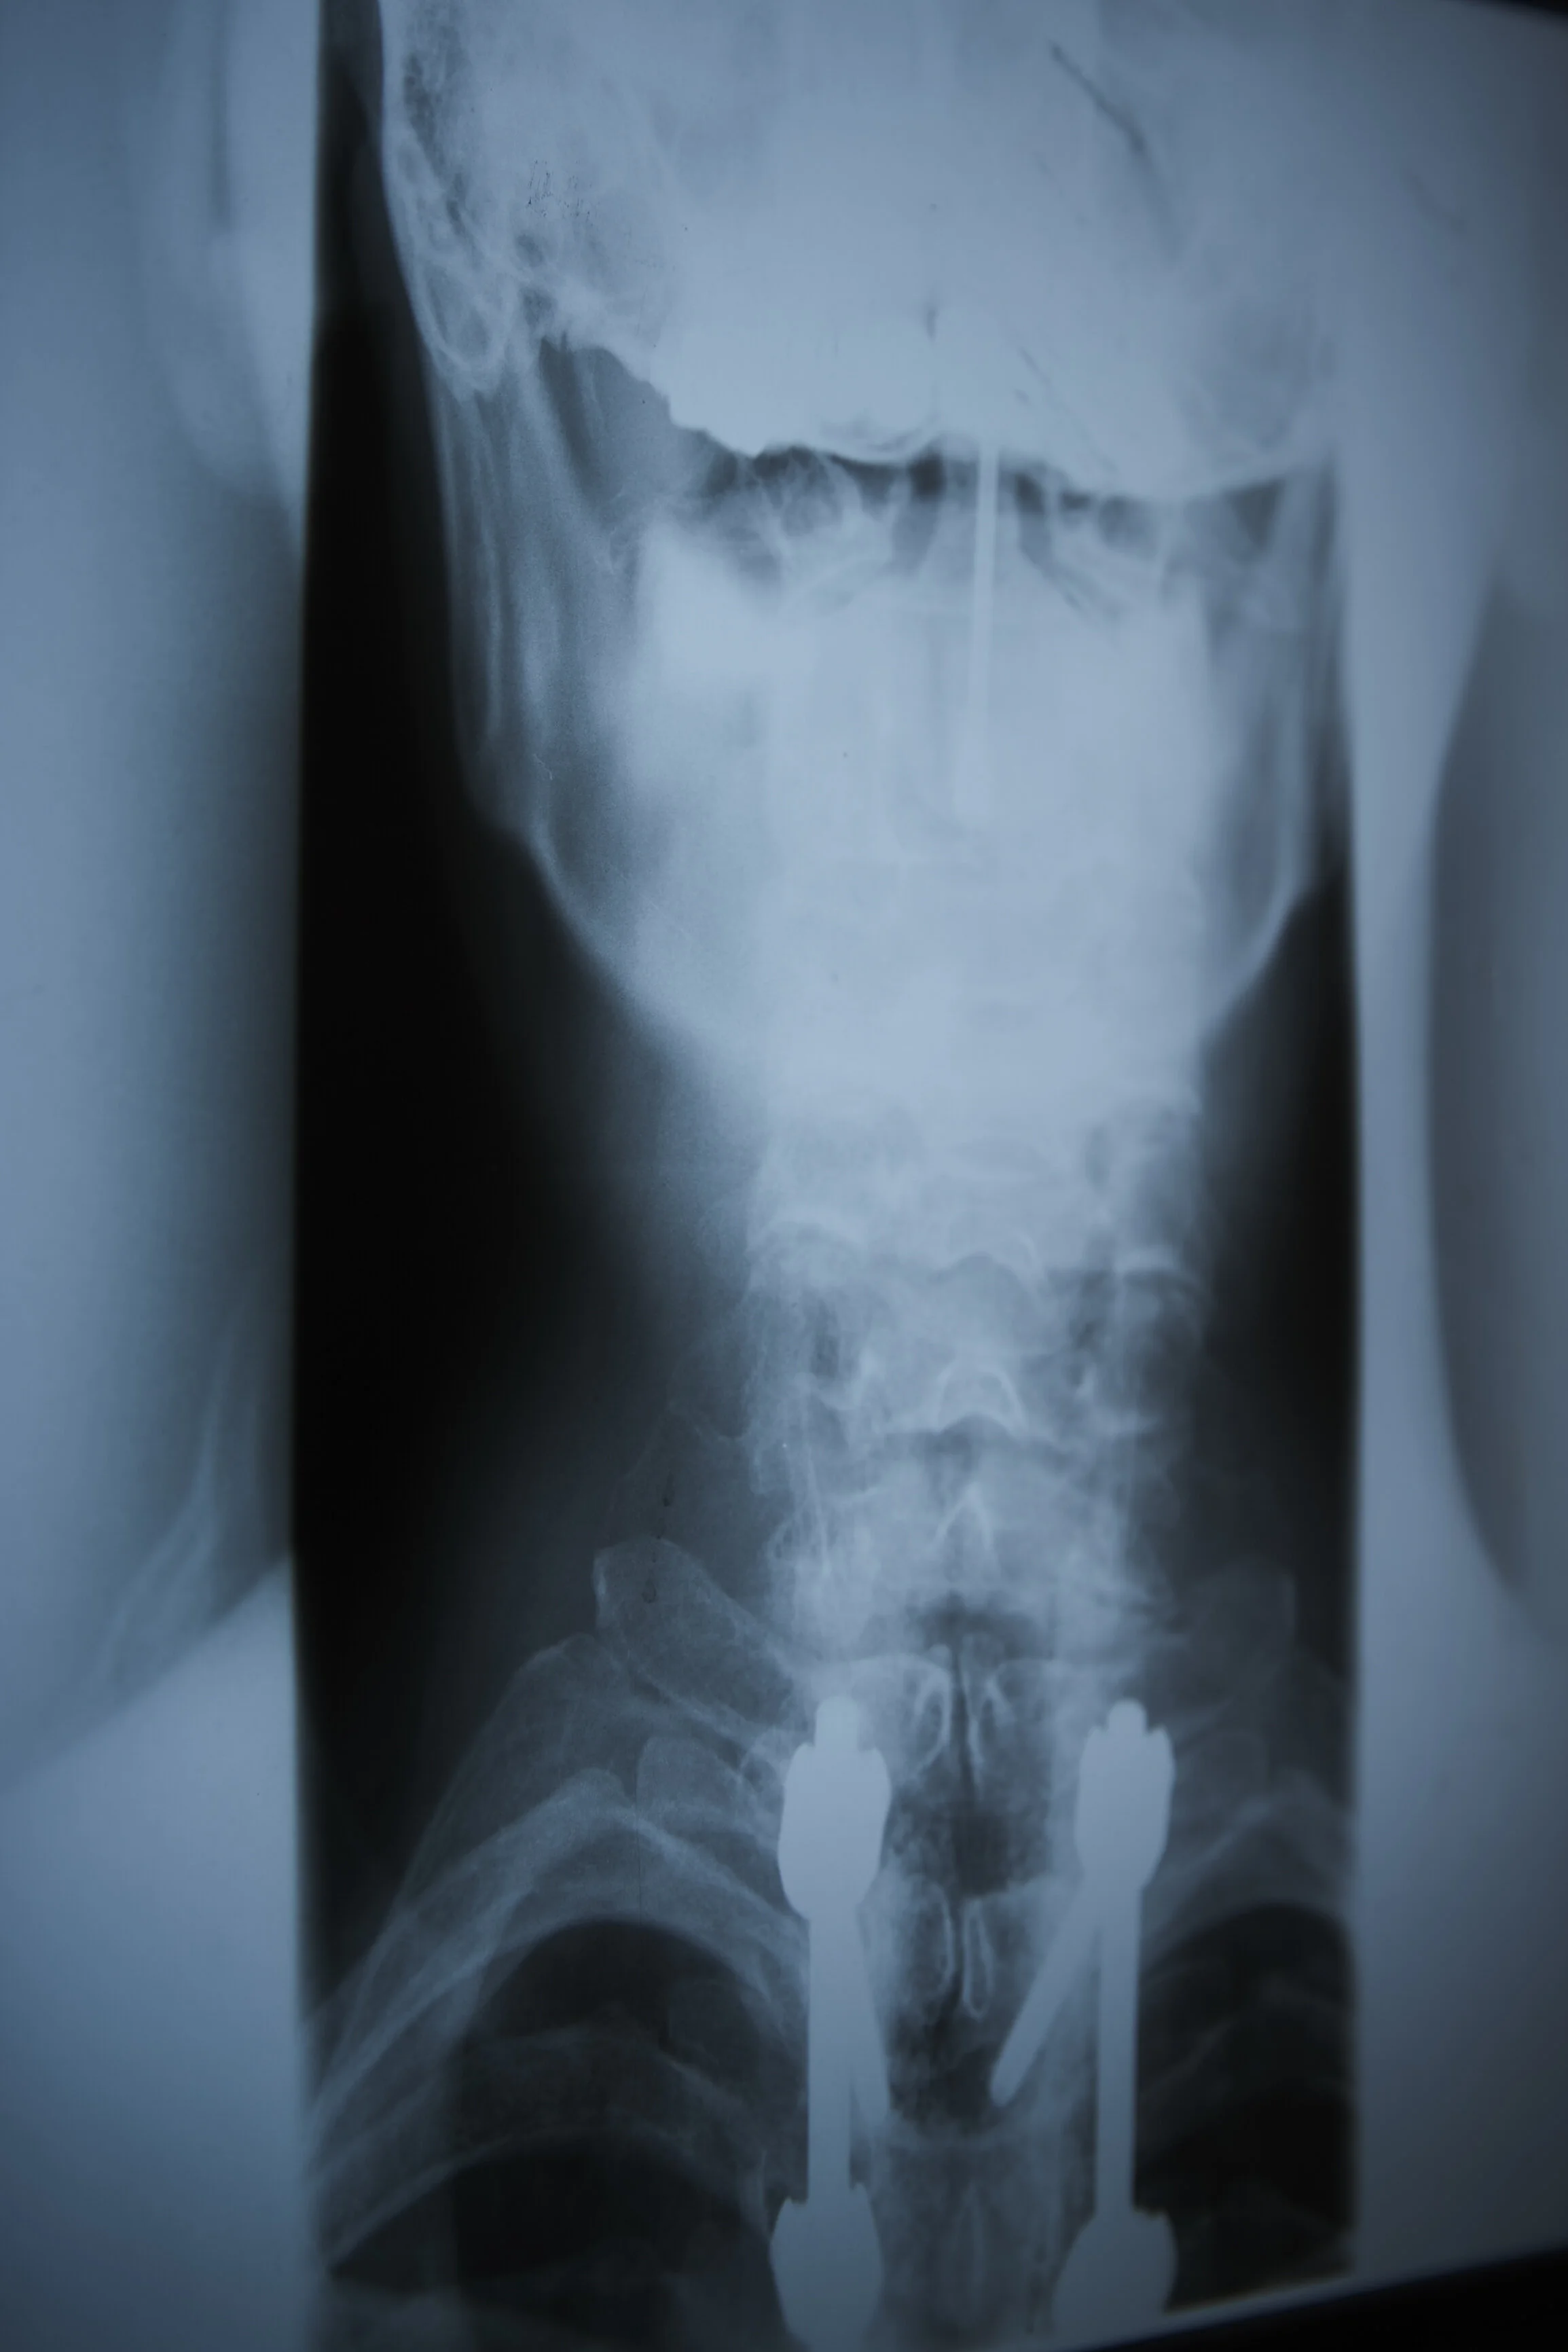

Röntgenaufnahme der Halswirbelsäule mit chirurgischen Implantaten.